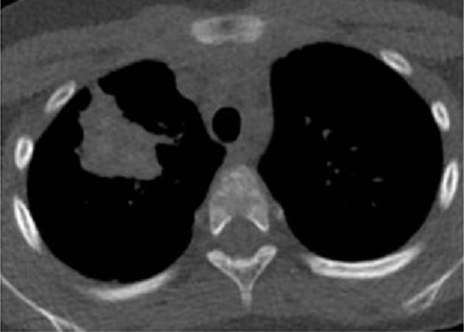

Aspect radiologique TDM

de masse isodensite paravertébrale gauche hétérogène

volumineuse, contenant des zones de densité négative,

graisseuse . Image radiologique TDM du thorax sans

contrast intraveineuse coupe axiale |

Aspect radiologique IRM thoracique

de cette tumeur en coupe axiale pondérée T1 .

Elle est isointense predominance de heterogene et

zone de hypersignal graisseuse . Image radiologique

IRM ponderee T1 en coupe axiale |